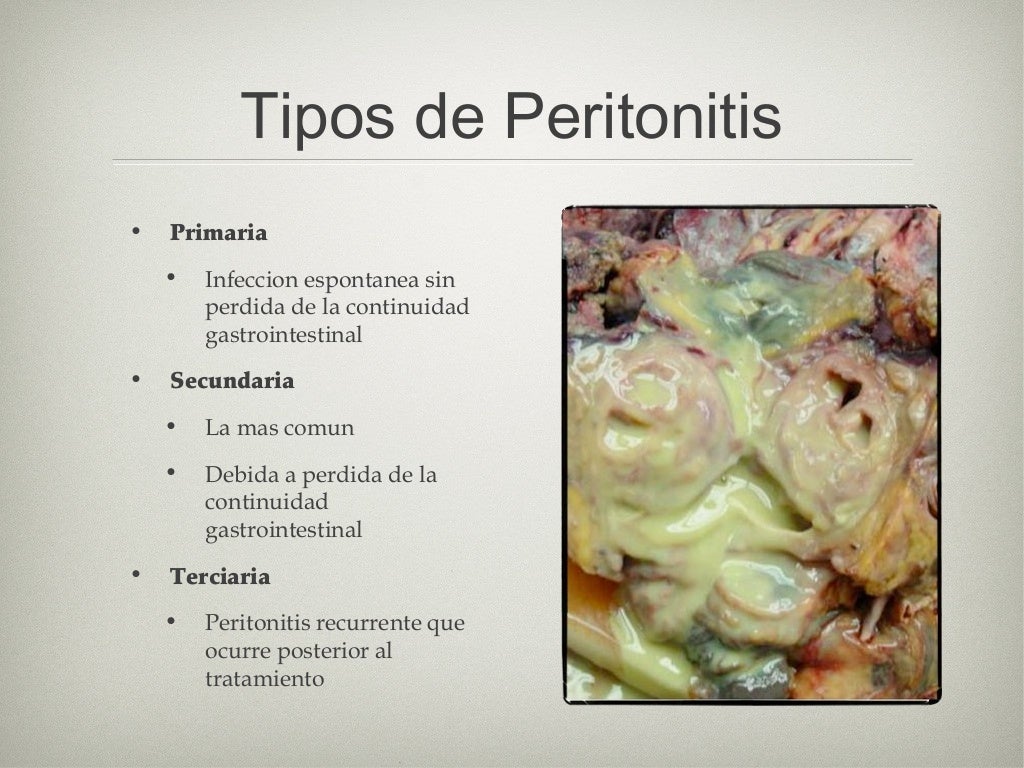

Sepsis intra abdominal

Source: es.slideshare.net

Sepsis abdominal fisiopatología, diagnóstico y tratamiento Medcmc

Source: med-cmc.com

Sepsis intra abdominal

Source: es.slideshare.net